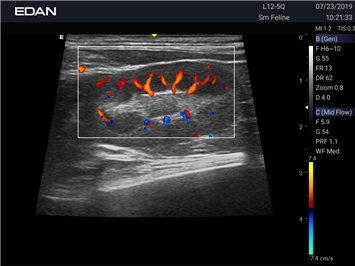

EDAN Acclarix AX2 VET представляет собой специализированную ветеринарную ультразвуковую систему, сочетающую высокую производительность с доступной ценой. Благодаря продуманной конструкции и передовым технологиям, система обеспечивает качественную диагностику животных различных видов.

Революционная платформа визуализации:

• Высокое разрешение для детальной диагностики

• Улучшенная визуализация глубоко расположенных органов

• Технология адаптивной визуализации тканей:

• Непрерывная автоматическая оптимизация изображения

• Адаптация к особенностям анатомии разных видов животных

• Повышенная точность исследований

Цветовой допплер:

Да

Энергетический допплер: